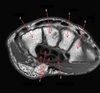

8

Q

What is letter B?

A

HEAD OF HUMERUS

How well did you know this?

1

Not at all

2

3

4

5

Perfectly

9

What is letter C?